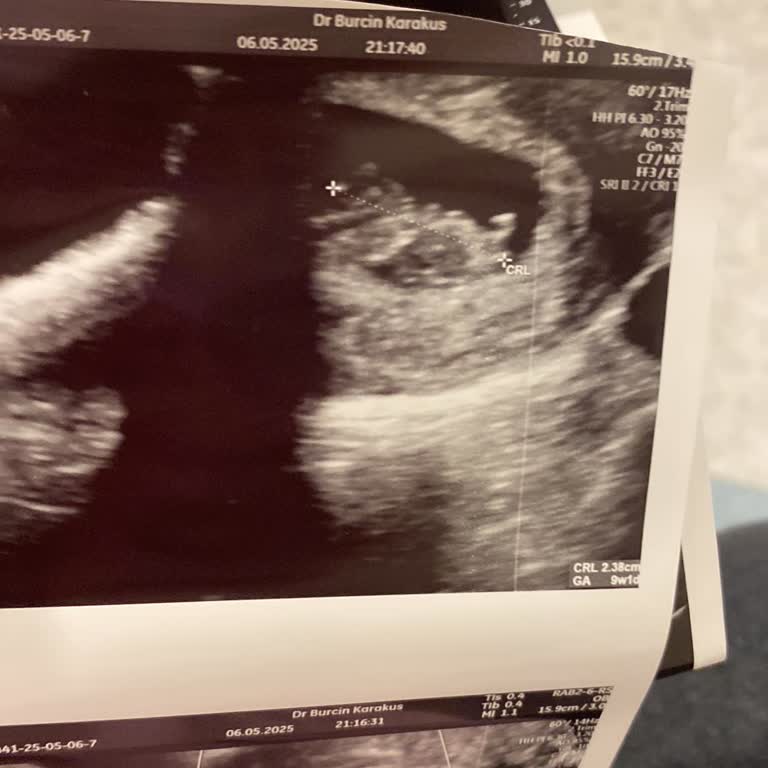

Ben daha birkaç hafta önce hamile olduğumu öğrenmiş bir kadınım. Ani kanamam ile 06/12/2024 sabah saatlerinde Bağcılar ilçesinde bulunan Medipol Mega Hastanesi’nde Op. Dr. S*** Y***** isimli bir doktora muayeneye gittik. Doktor, hiç muhatap bile olmadan, 5 haftalık bir bebeğin kalp atışını duyamayacağımızı belirtmeden, sadece karından ultrason ile bebeğin 5 haftalık olduğunu ama öldüğünü ve acilen kürtaj yapılması gerektiğini söyledi. 'Bir umut aramayın ama Salı gününe kadar bekleyin çünkü bebek ölmüş, bu durum değişmeyecek' diyerek Salı günü kürtaj olmam gerektiğini belirtti. Bu durum başta eşim ve beni, sonrasında tüm ailemi özellikle psikolojik olarak sarstı. Sonrasında 07/12/2024 tarihinde özel bir kliniğe giderek başka bir kadın doğum doktoruna danıştık. Doktor adı altında insanlara hizmet verdiğini düşünen S*** Hanım'ın aksine, biraz daha beklememizi, bebeğin henüz anneyi zehirleyecek durumda olmadığını ve zaten bu kadar erken bir zamanda bebeğin kalp atışını duyamayacağımızı söyledi. Bir haftalık süre sonrasında tekrar klinikteki doktora gittiğimizde bebeğin kalp atışını duyduk ve gayet sağlıklı olduğunu öğrendik. İnternette de Dr. S*** Hanım’ın birçok şikayetine rastladım, daha önce çocuk çetesi adı altında çalışan Bağcılar Özel Şafak Hastanesi’nde çalıştığını öğrendim. Bana yaptığı gibi başka hastalara da bebeğin öldüğünü veya çok hasta olduğunu söyleyip sırf para hırsı için kürtaja yönlendirdiğini öğrendim. Sağlık durumu başka doktorlar tarafından çok iyi denilen bebekleri bile boş yere günlerce anne sütünden uzak bir şekilde Şafak Hastanesi’nde yoğun bakımda yatırdığını şikayetler arasında gözlemledim. Benim psikolojimin bozulduğunu, bebeğimin kalp atışını duymama rağmen halen diken üstünde oluşum tamamen Op. Dr. S*** Y***** yüzündendir. Kendisinin internette de görüldüğü üzere şikayetlerini okuduğumda çocuk çetesine çalıştığını düşünmekteyim. Bu doktor kisvesi adı altında çalışan ama sadece gözünü para bürüyen Dr. S*** Y*****’dan şikayetçiyim. Kalbi atan bir bebeğin öldüğünü söyleyecek kadar ve kadınları anne gibi değil para gibi görecek kadar doktorluktan uzak bir kadındır. Eğer kürtaja gitmiş olsaydım şu an karnımda kalbi atan bebeğimin hayatına son vermiş olacaktım, haberim olmadan. Tüm gerekli işlemlerin yapılmasını istiyorum. Böyle doktorların başka kadınlara, özellikle de yıllardır çocuk hasreti çeken kadınlara, bu kadar kolay bir şekilde sırf para uğruna bebeklerin hayatlarına son veren bir doktordur.